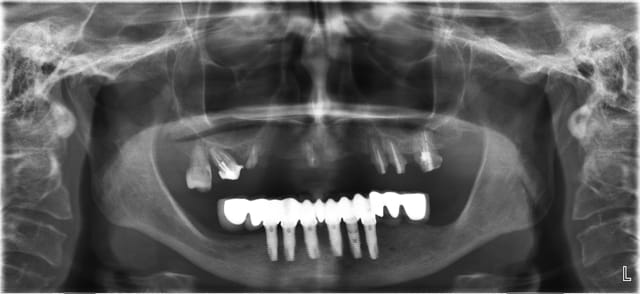

Sans scan (ou je l'ai loupé à la relecture du post) je n'émettrai aucun avis sur une simple pano. Toutefois même avec quelques coupes en exemple c'est trop difficile sur ce site de se faire une vraie idée. Le seul et vrai moyen serait de demander à positdental lui même en envoyant le Cd en Dicom.

Maintenant voilà un cas réalisé(ressemblant au tien je pense); avec la pano avant et la pano à trois mois! La patiente est ressortie du cabinet 5 heures après avec ses dents. J'ai fait refaire un scan à la patiente pour avoir la position des implants et faire la comparaison entre la planif et le travail executé.

Je vais entendre hurler pxav car les implants ont été mis en distraction osseuse je dirai plutot en condensation... bref. A vous de voir!